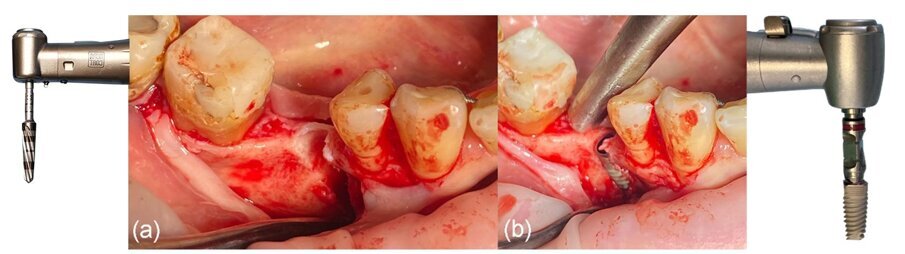

Dopo l’anestesia locale (Articaina con adrenalina1.200.00) l’accesso alla cresta edentula è stato fornito con una lama 15C utilizzando incisioni intrasulculari buccali e linguali dalla zona distale del dente 43 fino all’aspetto mesiale del dente 48, e un’incisione mid-crestale sul sito edentulo 46 (Fig. 3). Le aree delle papille interdentali sono state attentamente dissezionate a spessore parziale e sono stati sollevati con cura 2 lembi (buccale e linguale) (Fig. 4). Il lembo buccale è stato ulteriormente rilasciato con una incisione periostea utilizzando una lama 15 e uno scollaperiostio. Per il rilascio del lembo linguale si è ottenuto con un leggero stiramento delle fibre del muscolo miloioideo mentre si tirava il lembo verso l’alto (Fig. 5). È stato eseguito un’operazione di preparazione con un protocollo di espansione del margine alveolare utilizzando frese Densah (Versah) sul sito 46, ed è stato inserito un impianto MIS V3 con diametro di 4,3 mm e lunghezza di 10 mm (MIS Implants Technologies) 2 mm al di sotto del margine crestale con una coppia di serraggio di 35 N.cm, lasciando una significativa deiscenza vestibolare (Fig. 6). Un moncone singolo (moncone di connessione con diametro di 5,7 mm e altezza di 2 mm, MIS Implants Technologies) è stato collegato all’impianto con una coppia di serraggio finale di 30 N.cm (Fig. 7).

Fig. 6_a) Deiscenza vestibolare dopo la perforazione, b) situazione clinica dopo il posizionamento dell’impianto.

Fig. 7_Moncone di connessione in situ: a) vista occlusale, b) vista vestibolare.